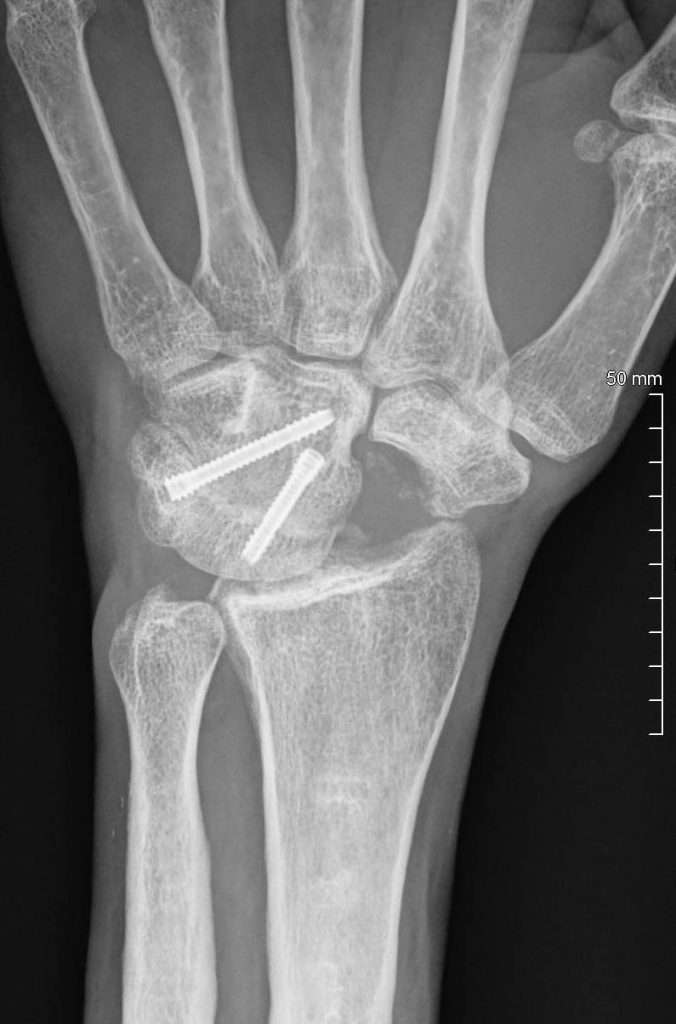

Los objetivos del tratamiento son calmar el dolor, conseguir la mejor funcionalidad de la muñeca y mano posible y prevenir la artrosis.  Generalmente, es necesario el tratamiento quirúrgico para limpiar y legrar el foco de la fractura para poder poner algún tipo de injerto óseo y estabilizar la fractura con agujas o tornillos (Figura 3).  Dentro de las opciones quirúrgicas se incluyen también la estiloidectomía del radio, la carpectomía proximal, le extirpación del escafoides y artrodesis o fusión parcial de la muñeca (Figura 4) e incluso la artrodesis o fusión total de la muñeca, dependiendo entre otras cosas del grado de degeneración artrósica de la muñeca asociada a la pseudoartrosis.

PATOLOGIAS MUÑECA - PSEUDOARTROSIS DE ESCAFOIDES Figura 3 - Rx postquirúrgica pseudoartrosis escafoides con injerto

Figura 3 - Rx postquirúrgica pseudoartrosis escafoides con injerto.